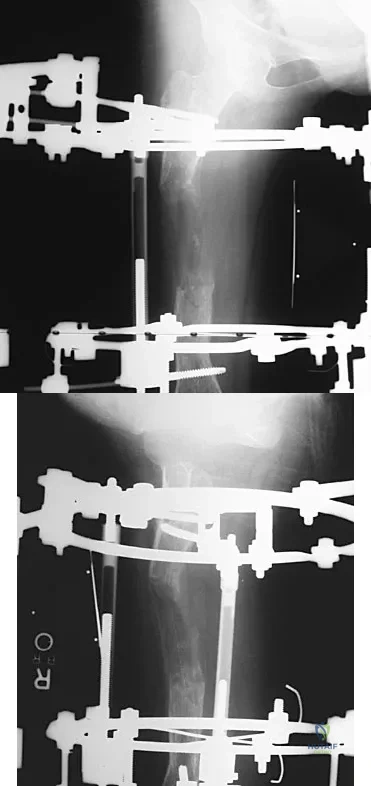

Figures 45a and 45b show the AP and lateral radiographs of a 15-year old patient who is undergoing surgery to add 3 cm of length to the femur. Based on the radiographic findings, what is the next most appropriate step in management?

Explanation